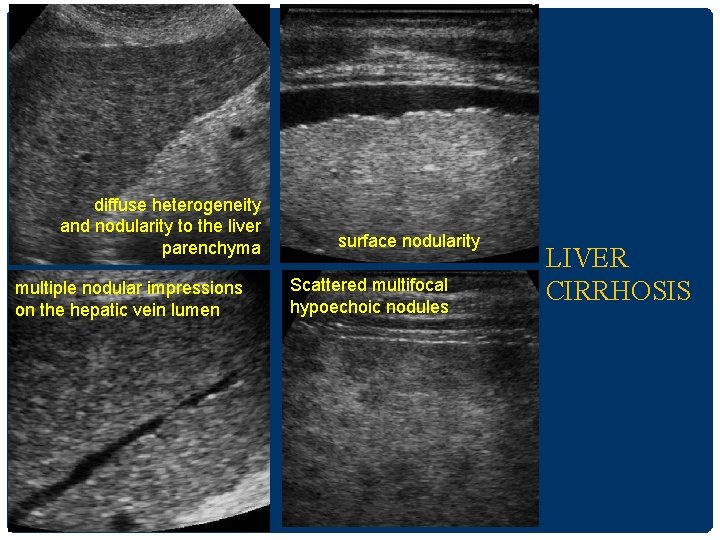

CIRRHOSIS • US appearance • Surface nodularity reliable sign • Coarsening and nodularity of the liver parenchyma(RN/DN) • Segmental hypertrophy/atrophy • Hypertrophy of the caudate lobe and lateral segments of left lobe (S 2&3) • Atrophy of the posterior segments (S 6&7) of the right lobe • RL: LL(longitudinal ratio) < 1. 3 (normal =1. 44) • Signs of portal hypertension

diffuse heterogeneity and nodularity to the liver parenchyma multiple nodular impressions on the hepatic vein lumen surface nodularity Scattered multifocal hypoechoic nodules LIVER CIRRHOSIS